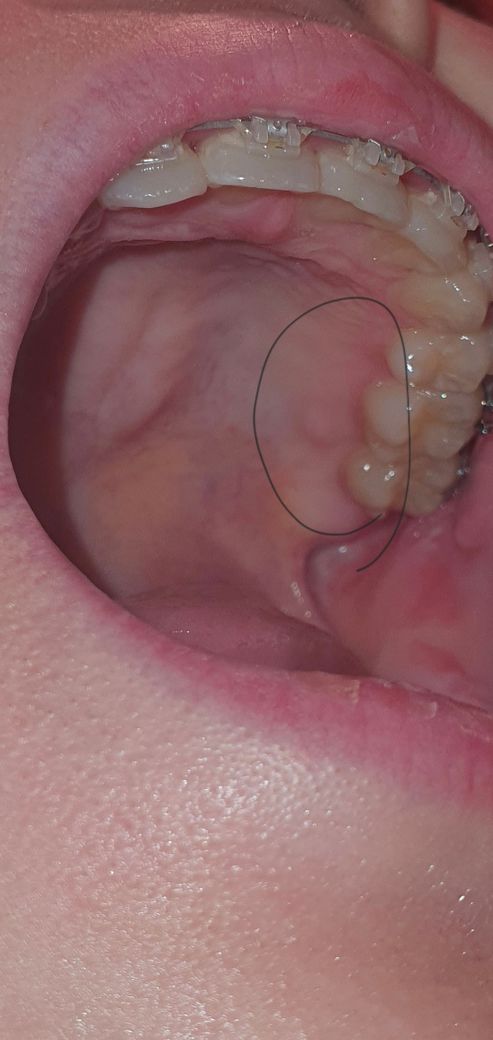

제가 치과 교정을 하고있는데요 우선 앞니쪽 잇몸에는 뾰족뾰족 골융기가 많이 보인다고 하셨는데 최근에 문뜩 입천장을 혀로 만져보니 TPA? 를 끼고있었어서 몰랐는데 어금니쪽 안쪽에도 아프진랂고 딱딱한게 만져지더라고요 근데 검색을 해보니 골융기는 입천장 중앙에 생기는 것 같던데 저것도 골융기일까요? 암은 아니겠죠?? 담배도 술도 안합니다 ㅠㅠ

상악은 저부위에 골융기가 잇진 않습니다.아마 교정장치를 떼고나서잇몸이 부은거같은데 시간이 지나면 괜찮아 지실꺼에요

사진으로 보이는 부위는 골 융기일 수도 있지만 그냥 잇몸이 자라나온 걸 수도 있습니다.

해당 부위에 골 용기는 크게 문제를 발생시키지 않기 때문에 자극하지 않는 것이 불편감을 줄일 수 있습니다.